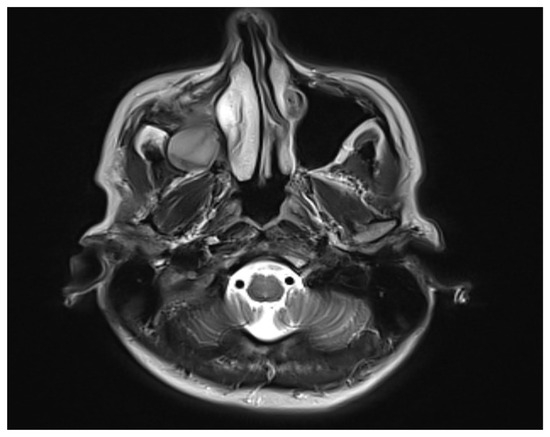

2. Case Presentation